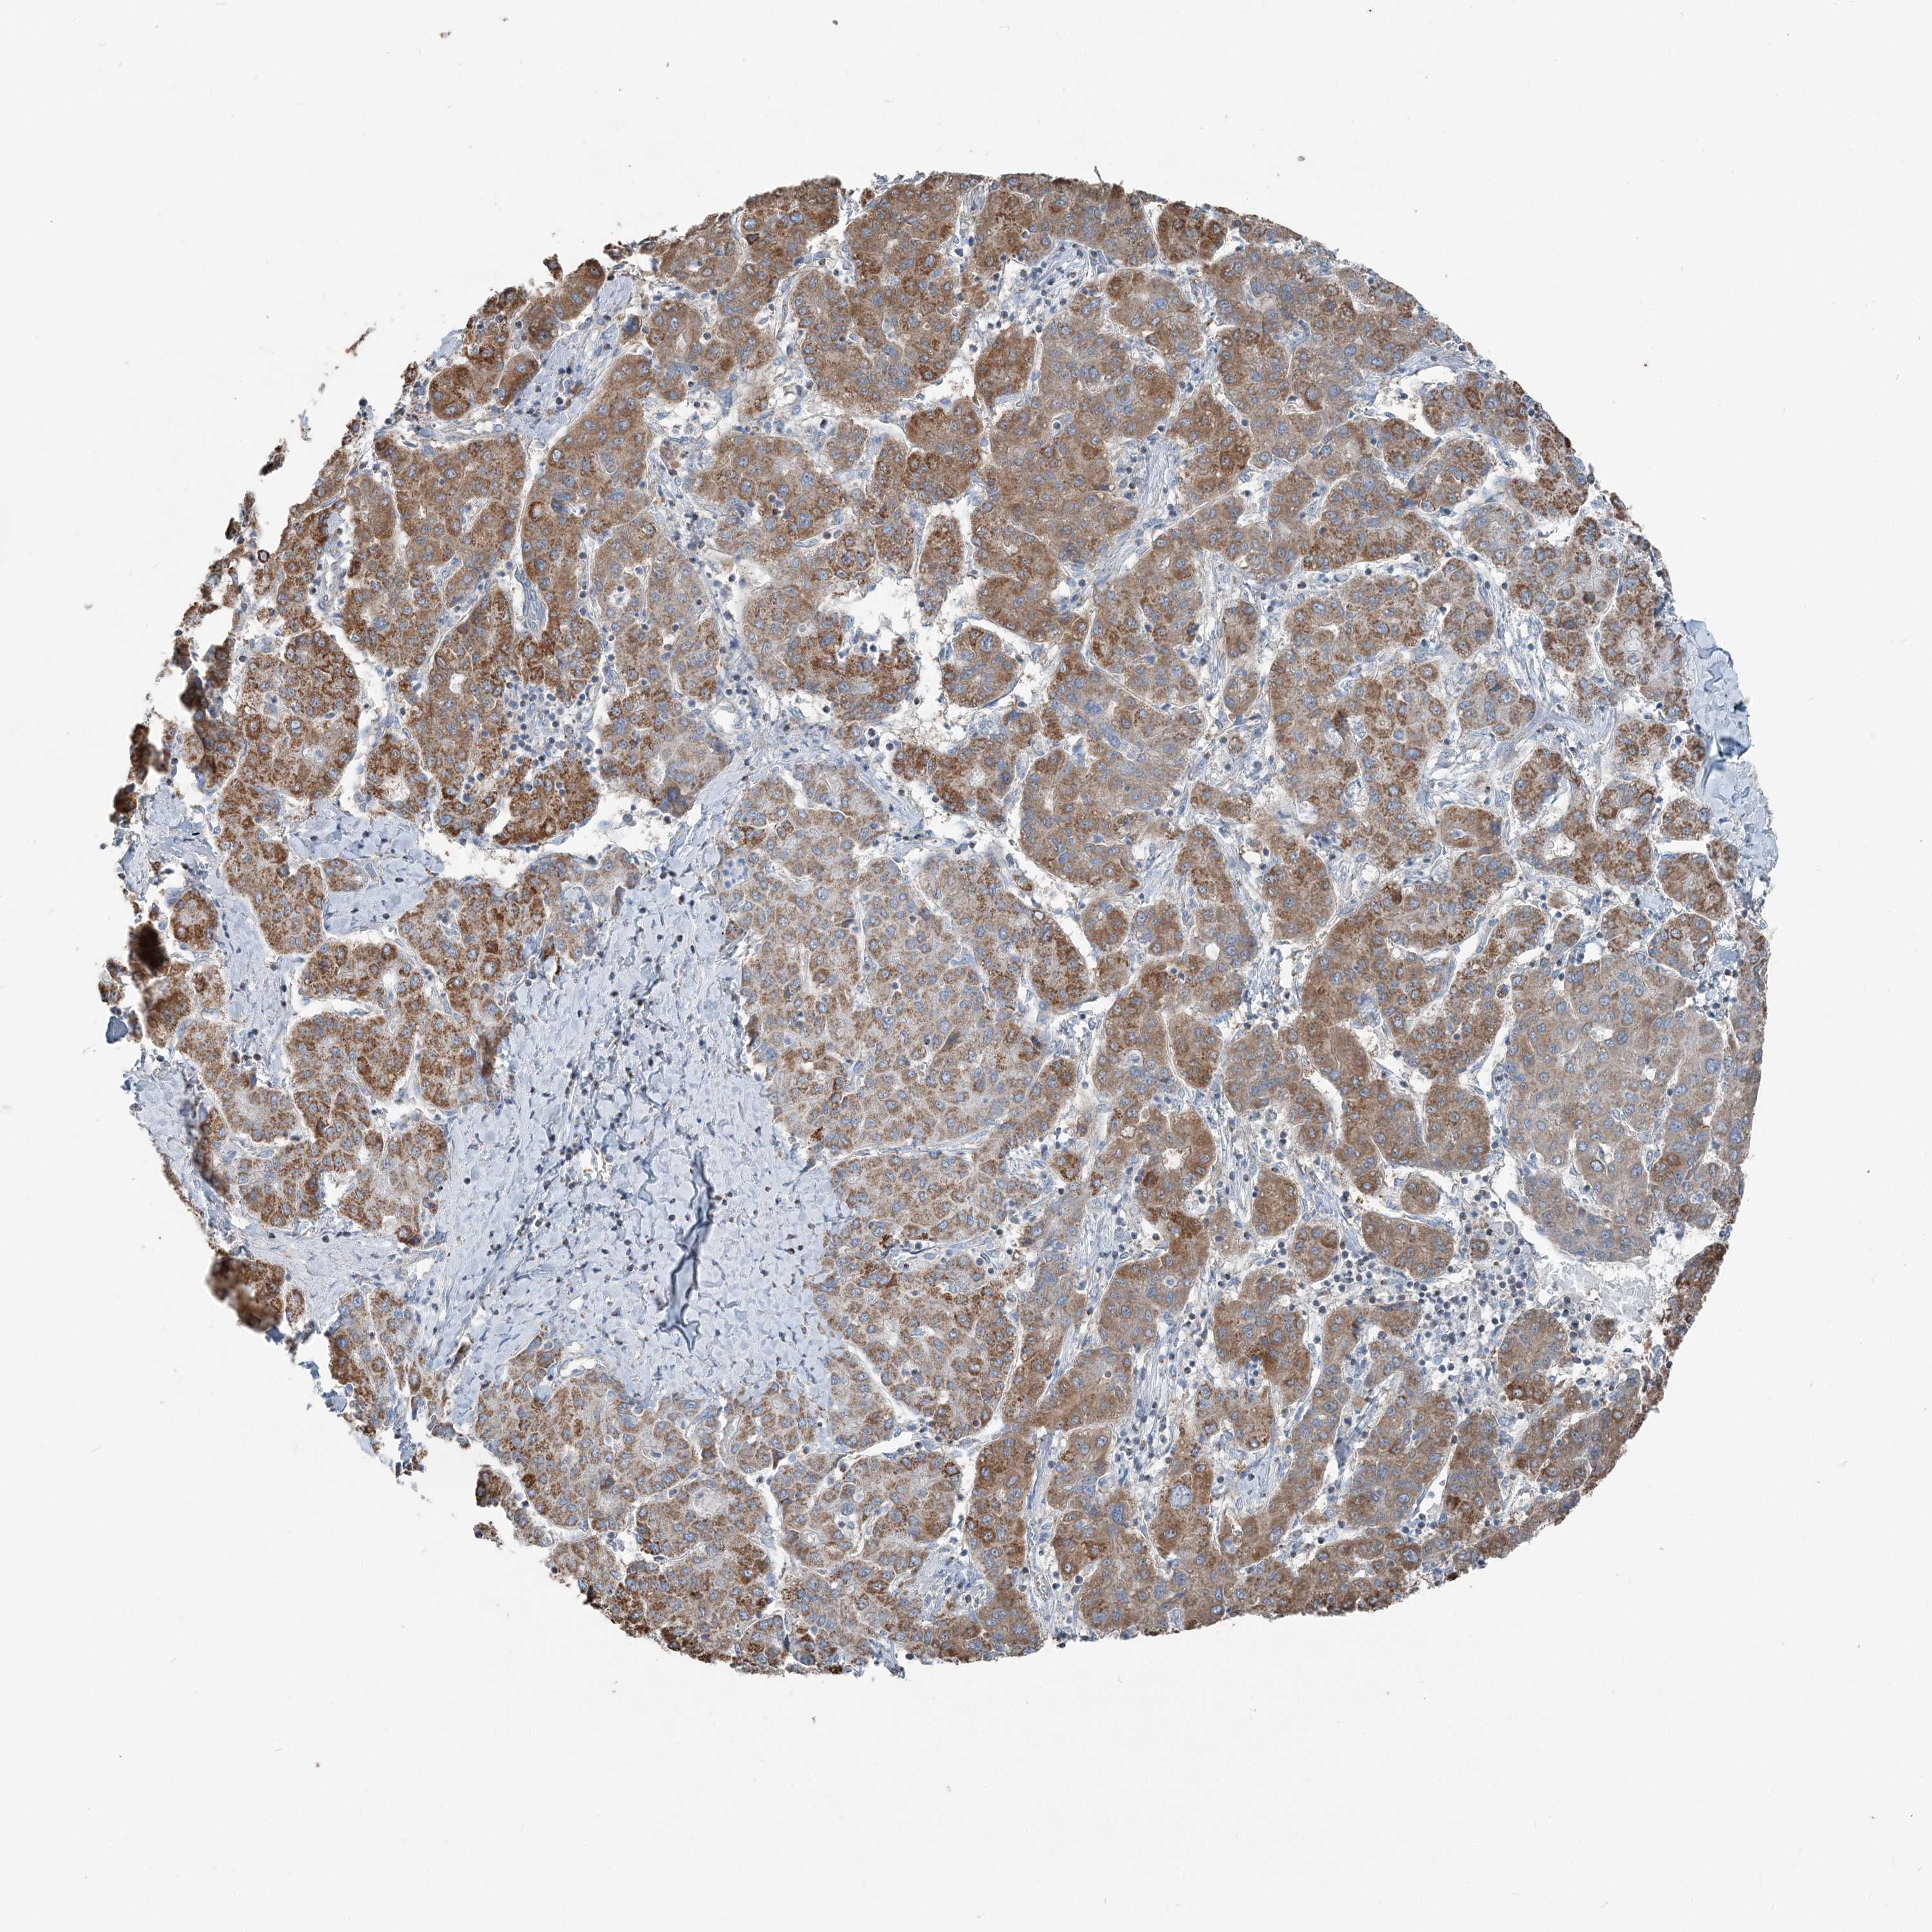

LIVER CANCER - Protein expressioni

A mouse-over function shows sample information and annotation data. Click on an image to view it in a full screen mode. Samples can be filtered based on level of antibody staining by selecting one or several of the following categories: high, medium, low and not detected. The assay and annotation is described here.

Note that samples used for immunohistochemistry by the Human Protein Atlas do not correspond to samples in the TCGA dataset.

Antibody stainingi

Antibody staining in the annotated cell types in the current human tissue is reported as not detected, low, medium, or high, based on conventional immunohistochemistry profiling in selected tissues. This score is based on the combination of the staining intensity and fraction of stained cells.

Each image is clickable and will lead to virtual microscopy that enables deeper exploration of all samples and also displays staining intensity scores, fraction scores and subcellular localization as well as patient and tissue information for each sample.

Antibody HPA036683

Antibody HPA036684

Staining

High

Medium

Low

Not detected

Intensity

Strong

Moderate

Weak

Negative

Quantity

>75%

75%-25%

<25%

None

Location

Nuclear

Cytoplasmic/membranous

Cytoplasmic/membranous,nuclear

Cholangiocarcinoma

Carcinoma, Hepatocellular, NOS